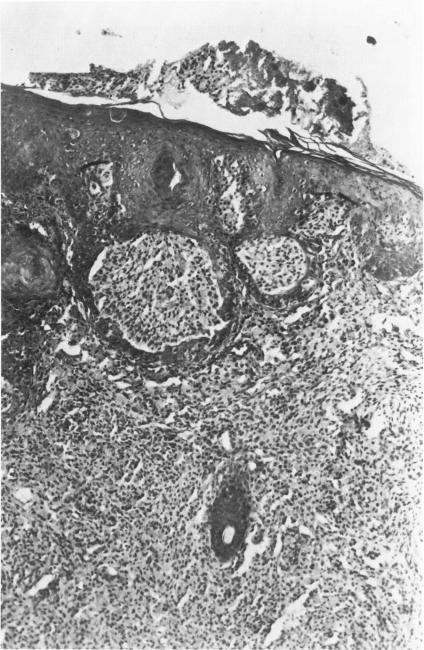

Previous studies have demonstrated pathologic similarities between human melanoma and the spontaneous melanoma in the Sinclair miniature swine (SMS) with respect to cutaneous histologic features and patterns of metastasis. The current biopsy series, correlating growth curves and histopathologic features of cutaneous melanomas, was undertaken for documentation of the histologic events associated with the successful regression of melanoma in the SMS. Cutaneous growth and regression was characterized by a series of cellular events that eventually led to depigmentation and scar formation. Mononuclear inflammatory infiltrates, seen in over half of the 104 biopsies, showed several temporal and topographic distribution patterns, similar to that described in human melanoma. Histopathologic observations in the SMS confirm clinical observations that the host can, with consistent effectiveness, react with the tumors to modify their biologic aggressiveness. Although regression is associated with lymphocytic and macrophage infiltration, the exact role of the immune response in the regression of the cutaneous melanoma remains to be elucidated.